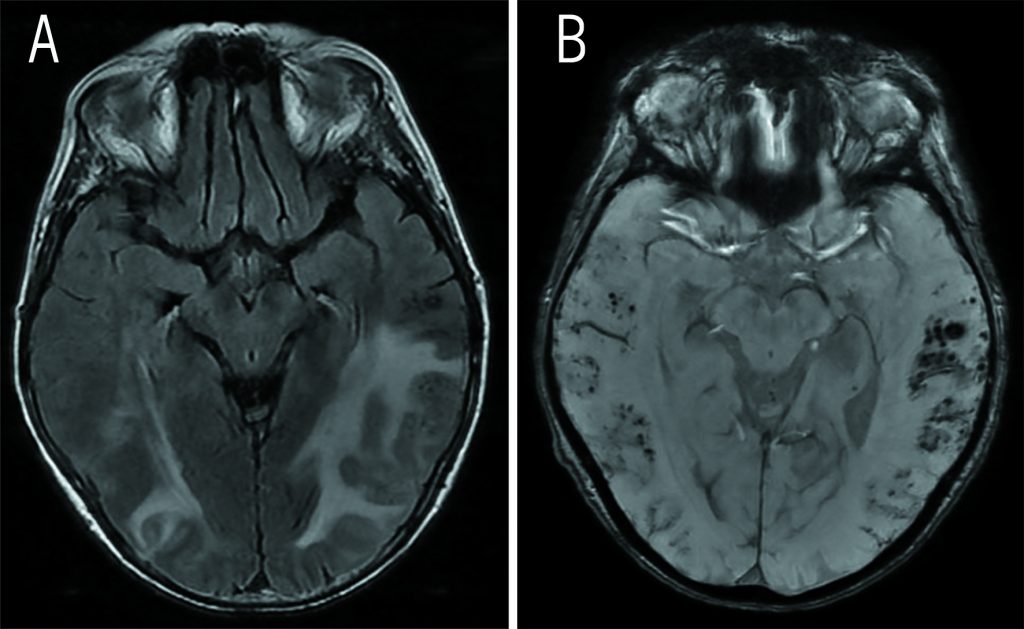

Les microhémorragies sont un marqueur d’une lésion cérébrovasculaire, qui se manifeste principalement dans les petits vaisseaux. Elles indiquent une tendance à l’hémorragie dans le cerveau et augmentent le risque d’hémorragie intracérébrale et d’accident vasculaire cérébral ischémique.

Cliniquement, le diagnostic repose sur la présence radiologique d’hémorragies lobaires uniques ou multiples à la jonction cortex-moelle ou de micro-hémorragies cérébrales sans autre cause plus probable. La présence d’une angiopathie amyloïde cérébrale est considérée comme probable,… Quel est le point commun du dépôt d’amyloïde ?